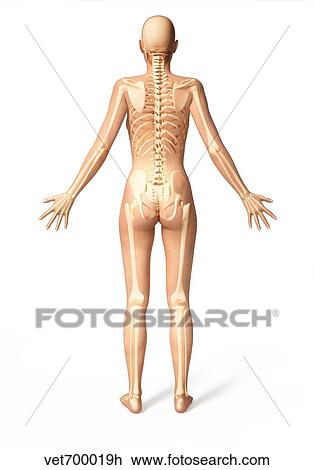

Female Standing With Skeletal Bones Superimposed Rear View

Female Standing With Skeletal Bones Superimposed Rear View

Human Figure Drawing Methods Female Anatomy Back Bones Drawing

Human Figure Drawing Methods Female Anatomy Back Bones Drawing